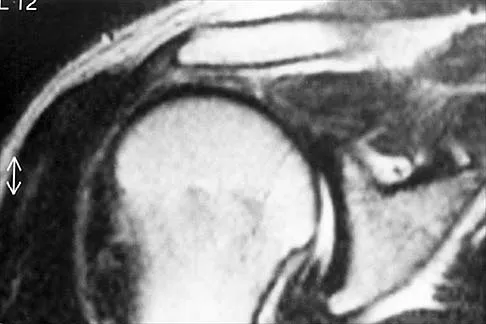

A 39-year-old competitive cyclist sustains an injury to her left hip in a fall. Gadolinium arthrography, with an accompanying MRI scan, is shown in Figure 31. A cleft, or defect, identified by the arrow, indicates a detachment of the